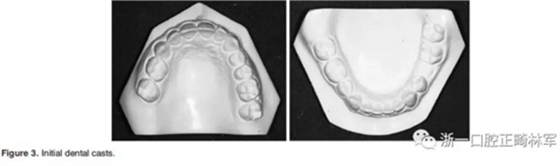

3.體格檢查:直面型,露齦笑,深覆合、合平面傾斜(Figure 1)。上中線偏右3mm,下中線偏左2mm。磨牙II類關(guān)系,左側(cè)尖牙II類關(guān)系,右側(cè)尖牙I類關(guān)系,左下第二磨牙低位咬合,右上前磨牙缺失。覆蓋率為100%,覆蓋度為4mm。咬合平面重度傾斜,左側(cè)向下移位(Figure 2、3)。

4.影像檢查:右上前磨牙和左下第二前磨牙缺失(Figure 4)。在另一名牙齒矯正醫(yī)師治療4年后,患者在19歲時被轉(zhuǎn)診給我們。他的咬合特征與他的初始狀態(tài)非常相似(Figure 5)